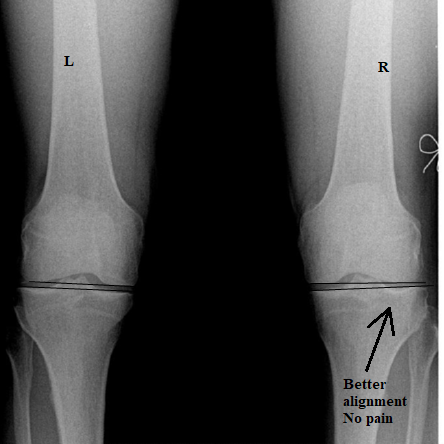

Having reached his 3 month mark of treatment, our Tauranga podiatrist referred for a follow up x-ray to measure the differences. You can clearly see there is a fantastic change in the before and after x-ray below. Jim is now back running 4 times a week with no pain and he has stated his fitness is back!